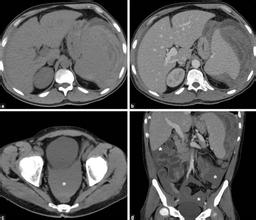

明白怎么回事,原来这是一个住院病人的家属,这个病人是大隐静脉曲张的病人,已经做完手术两周了,可是目前没有出院的原因就是因为患者在一周前不慎在病床上跌落下来,当时检查了CT,考虑肋骨骨折,脾脏挫伤,一直保守治疗,昨天晚上患者突然疼痛加重,早晨紧急检查了腹部CT,腹腔已经有大量的积液了,血常规贫血也比较重,这说明一个问题那就是需要紧急手术治疗。

那么脾脏损伤以后7天患者为什么还会再次出血。我们知道脾脏位于左上腹,脾脏是腹部最易受伤的实质性脏器,占各种腹部伤的40%~50%,脾脏破裂以后主要危险在于大出血,死亡率约10%,约85%为被膜和实质同时破裂的真性破裂,少数为中央型或被膜下破裂,其被膜尚完整,但可在2周内突然转为真性破裂而大量出血,称延迟性脾破裂,应予警惕。这例病人就是典型的迟发性脾脏破裂,患者突然腹痛说明脾脏被膜的压力增加,最终导致被膜破裂,大量出血。